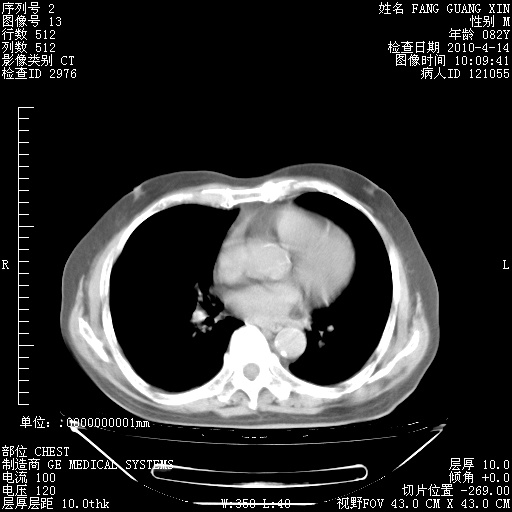

4月14日肺部CT

23.JPG

24.JPG

25.JPG

26.JPG

肺部CT平扫未见异常。